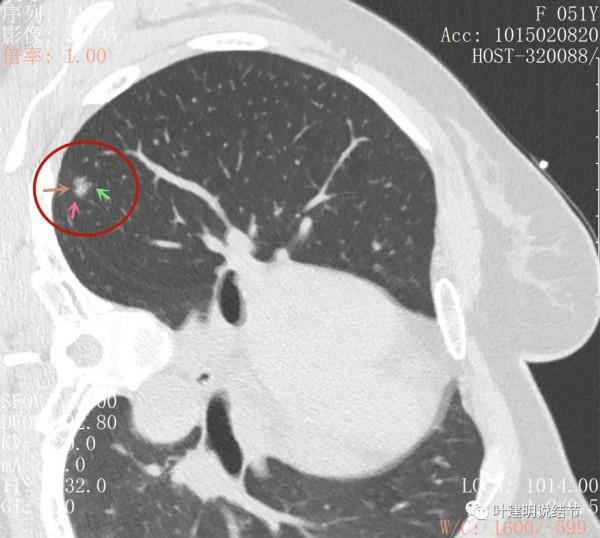

影象後處理與重建的影象顯示了更清楚的資訊,顯示主病灶(下稱A病灶)分葉(磚色箭頭)、有磨玻璃成分(綠色箭頭)以及實性成分(粉紅色箭頭)

病灶鄰近胸膜,密度雜亂

病灶實性佔比較多,輪廓清楚,胸膜有牽拉(藍色箭頭)

三維重建示病灶圓形類圓形

綜上所述,病軒A風險程度高,基本上應該是浸潤性腺癌,因為這麼小,是混合磨玻璃,且實性成分佔比較高,所以可能是至少腺泡型為主(也可能含更高風險亞型)伴貼壁成分(因為有磨玻璃成分,雖佔比少);B病灶考慮不典型增生可能性大,不能排除原位腺癌,若沒有A在,它可安全隨訪;C病灶考慮至少原位腺癌,也可能是微浸潤性腺癌,因為密度較高。若病為A在,它也因為過小,可隨訪。好在三個病灶都在上葉後段,那麼如果做上葉後段切除能一次解決目前所有病灶。所以我是建議其儘早手術的。今天要分享這個病例的目的還不是在這,而是我們再來看她2年前的片子,看病灶情況的演變,帶給我們的思考。先看其2年前的片子: